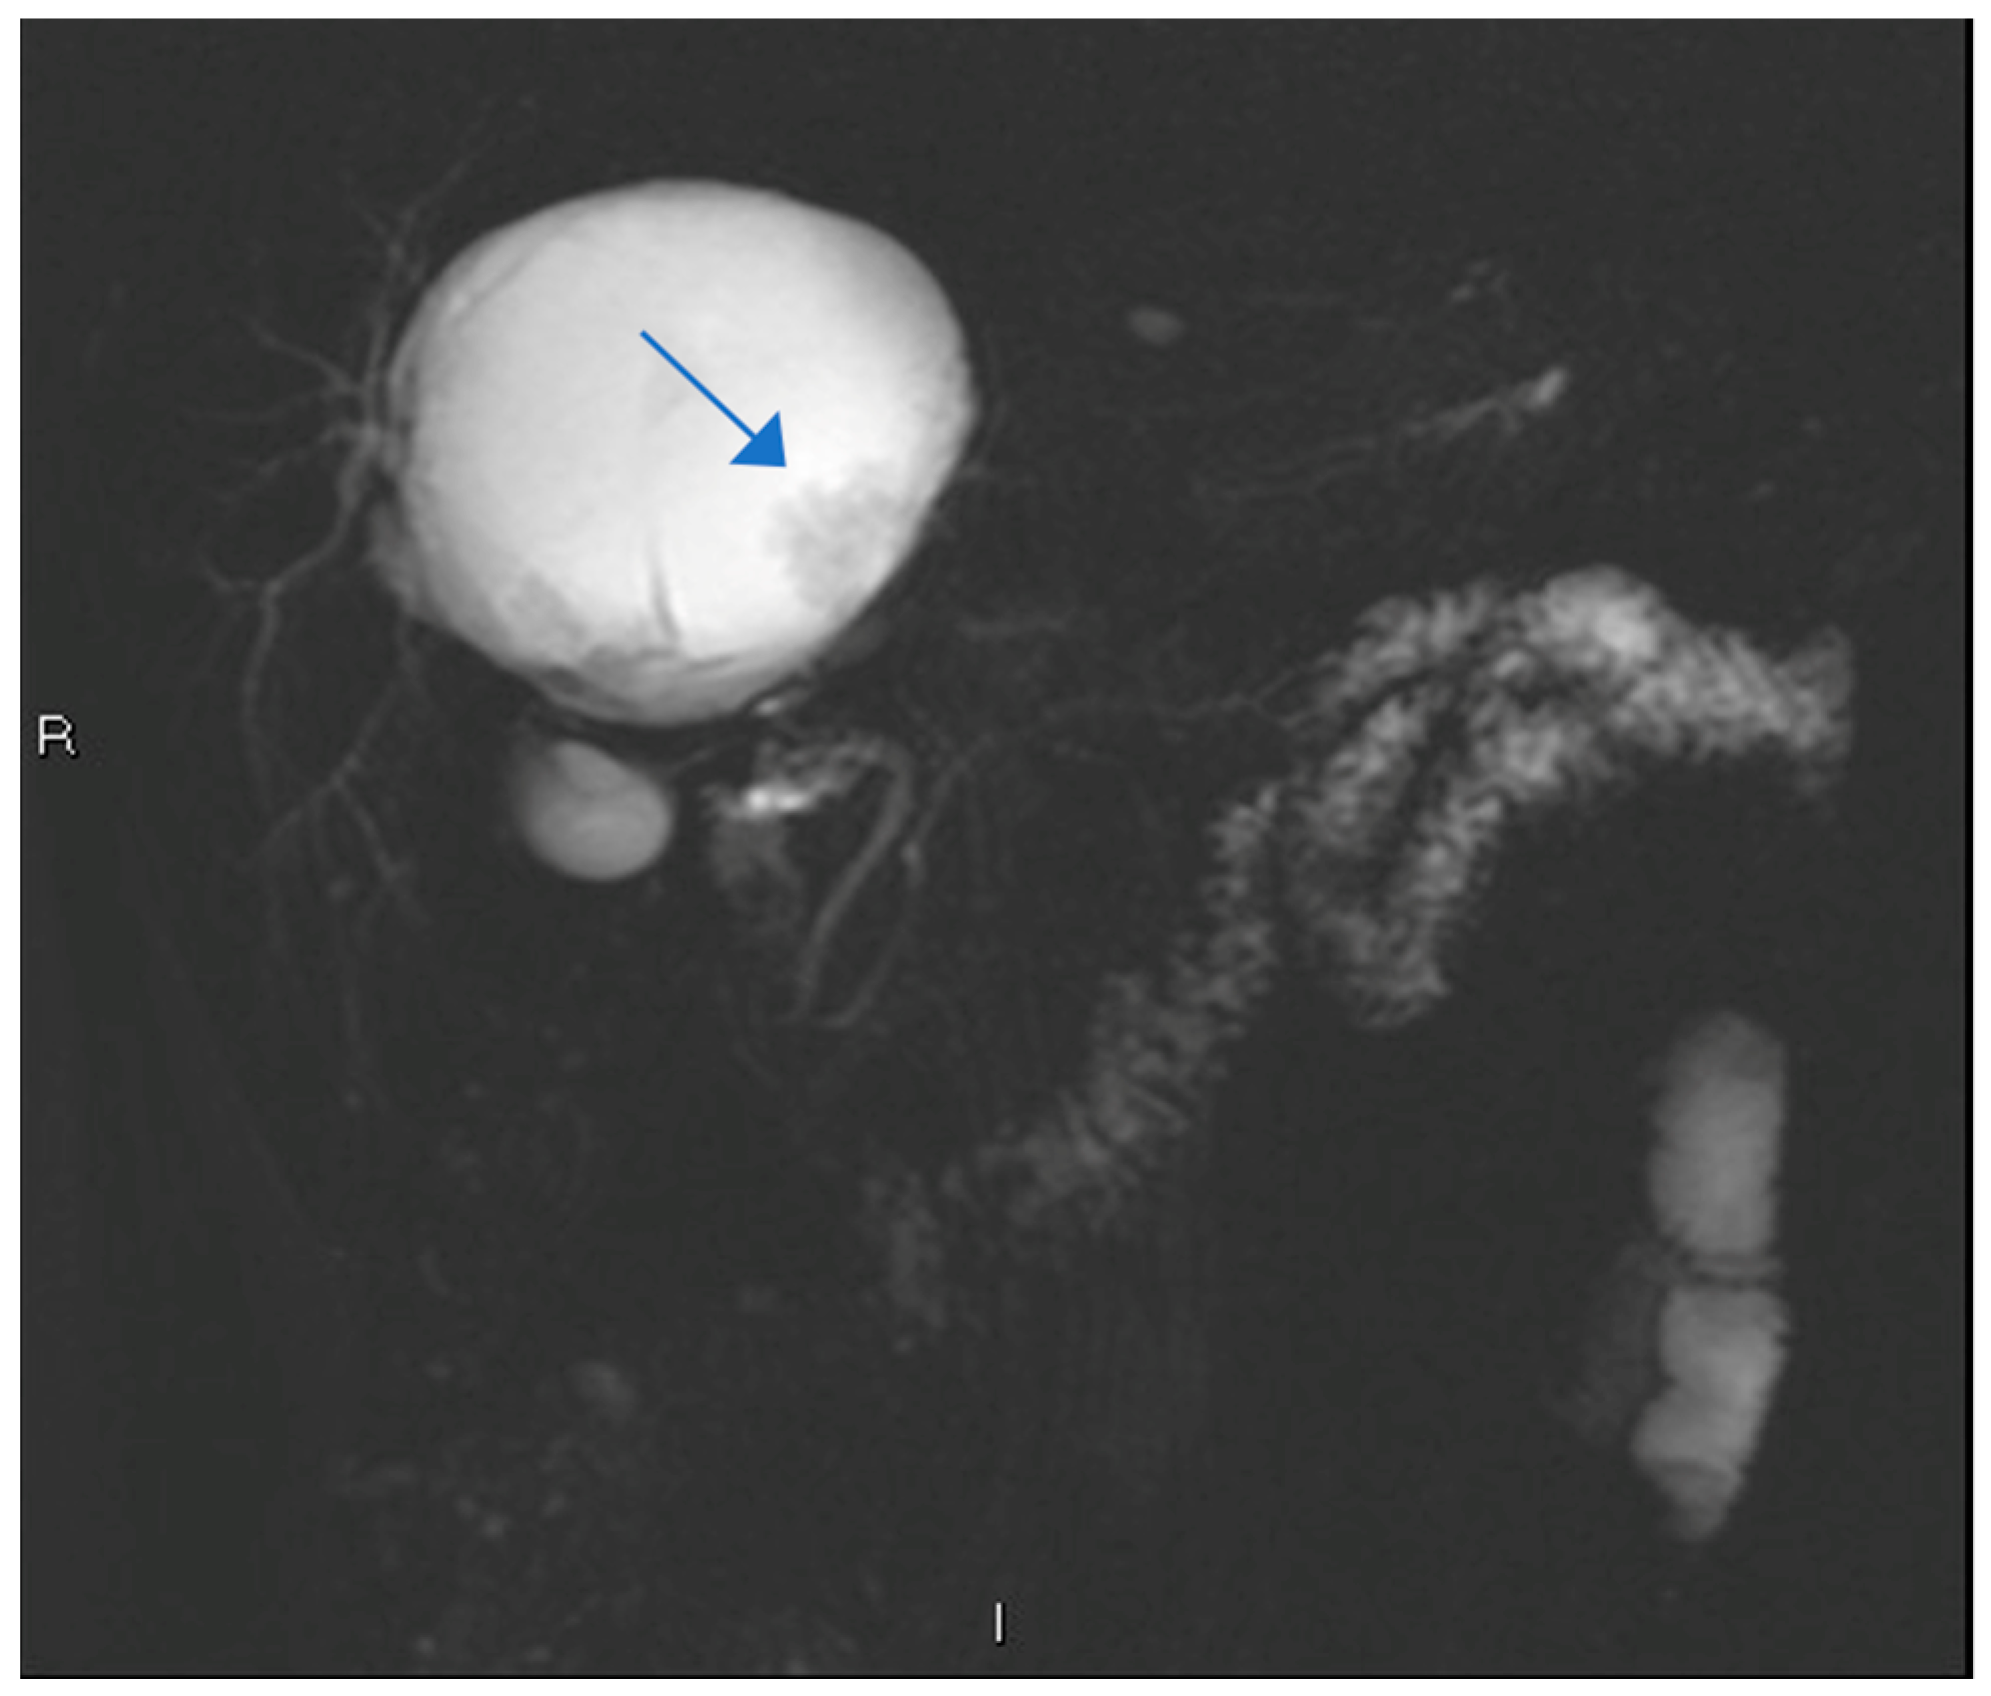

| Feature | Case 1 | Case 2 |

| Patient Demographics | 60-year-old Caucasian male | 28-year-old Caucasian female |

| Clinical Presentation | Incidental discovery of an 8 × 8 × 9 cm hepatic cyst | Presented with dyspnea, vomiting, jaundice, fever |

| Initial Diagnosis | Suspected hydatid cyst | Simple cyst, later adenocarcinoma with metastases |

| Diagnostic Methods | MRI, MRCP, ERCP, histopathological examination | CT, MRI, laparoscopic liver biopsy, histopathological examination |

| Tumor Characteristics | Large cystic mass, thin walls, internal septa, papillary projections, enhancing solid components | Large lesion in left hepatic lobe, hyperintensity in T2-weighted images, restricted diffusion, contrast enhancement |

| Treatment | Cyst resection, cholecystectomy | Thrombectomy, chemotherapy, supportive care |

| Surgical Findings | Partially exophytic floating soft mass | Extensive intrahepatic metastases, vascular involvement |

| Histopathological Findings | IPNB with foci of adenocarcinoma, oncocytic appearance, varying degrees of dysplasia, mucus within cyst | Adenocarcinoma with papillary clear cell and mucinous appearance, gland ectasis, cystic or pseudocystic aspects |

| Follow-up and Outcome | Initial recurrence-free survival for 8 years, recurrence treated with left hepatectomy, patient alive at 33 months post-second surgery | Disease progression despite aggressive management, patient died from hepatic failure |